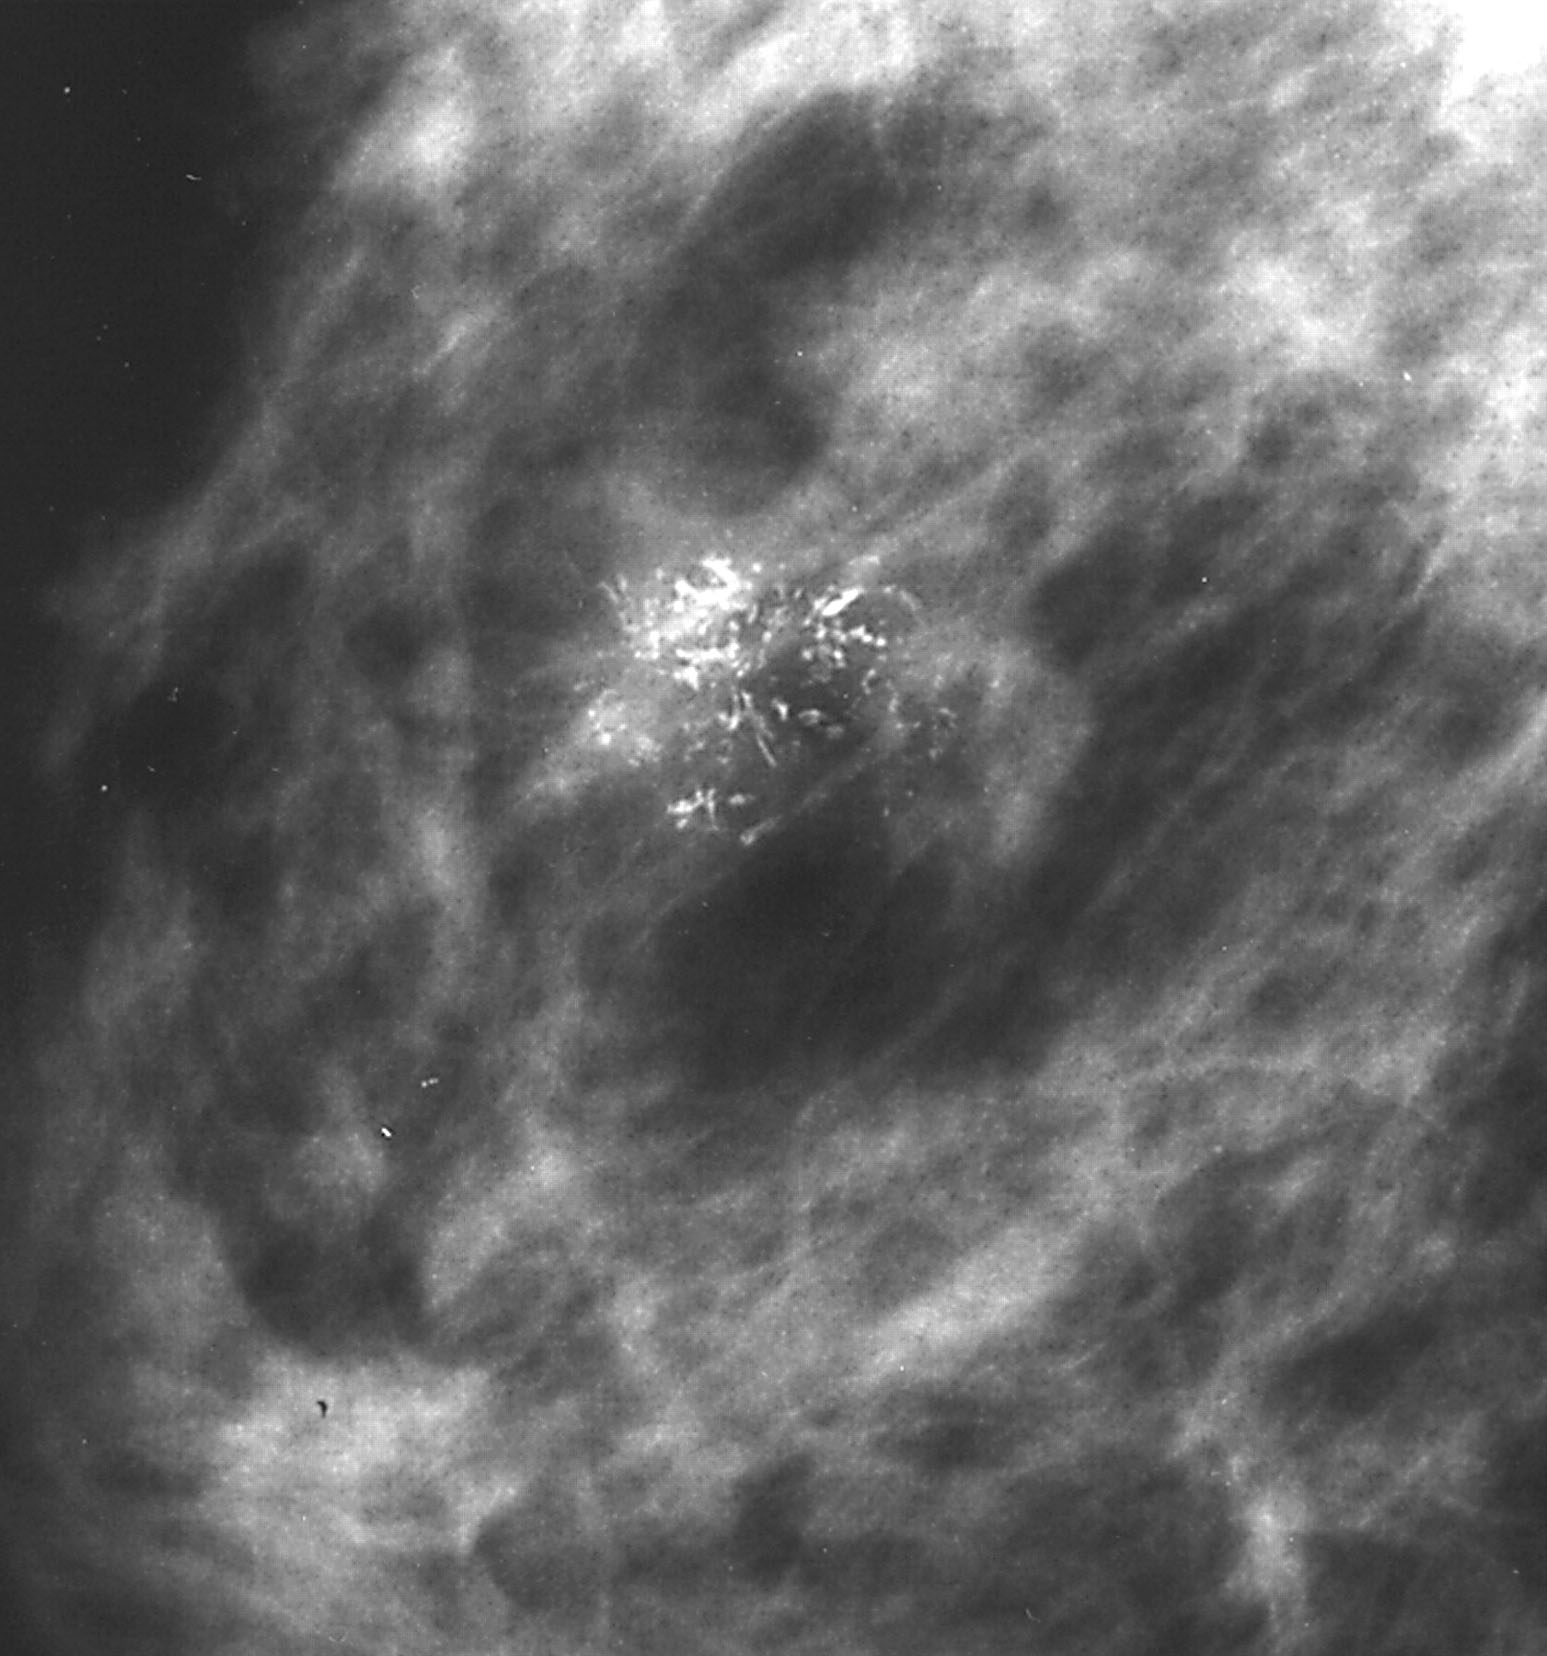

Radiology description

- Mammographically often presents as a spiculated mass with or without calcifications but may present as an architectural distortion or calcifications alone

- Targeted ultrasonography often used to enhance visualization

- MRI often shows enhancing mass lesion with variable washout kinetic patterns (Breast J 2010;16:394)

- MRI is sensitive but nonspecific technique is reserved for screening patients at high risk (e.g., BRCA mutation carriers), patients with dense breast tissue, estimating extent of disease in patients with lobular carcinoma, evaluating response to neoadjuvant chemotherapy or evaluating indeterminate abnormalities on mammography / ultrasound (Breast 2013;22:S77)